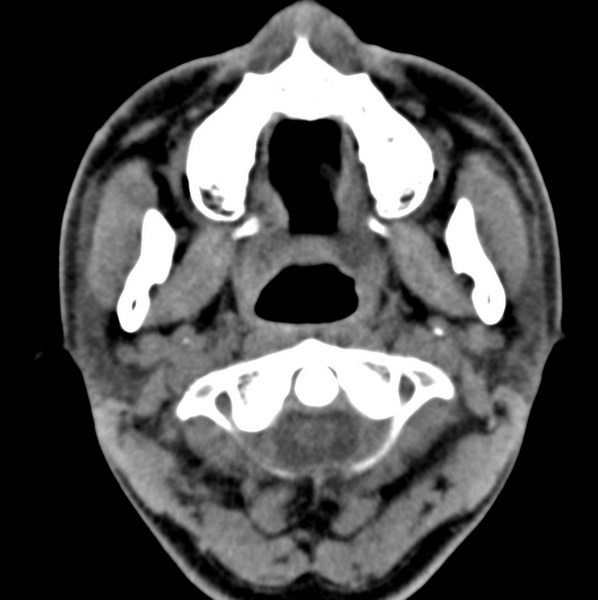

男、31、鼻咽部肿瘤放疗后请帮忙看看。

效果好,右侧破裂孔扩大,局部骨质缺损,为颅底骨质破坏。

1)鼻咽部肿瘤侵犯颅底放疗术后改变。2)左侧蝶窦炎。

咽后壁增厚,左侧咽鼓管隆突增大、咽鼓管咽口变浅,同侧咽旁间隙较窄。右侧颅底骨质破坏?为什么不在同一侧?

鼻咽部肿瘤侵犯颅底放疗术后改变.